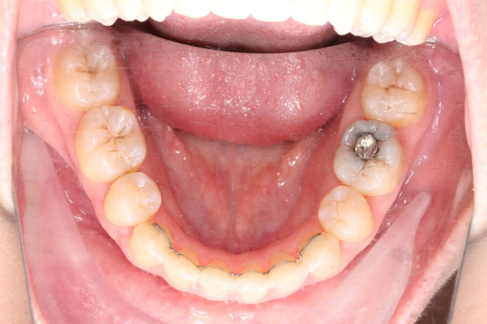

• 磨牙,尖牙I类关系,中线齐

• 上下牙列中度拥挤

• 上下前牙唇倾

2018.11.14  术后磨牙尖牙I类关系,中线齐,覆合,覆盖正常